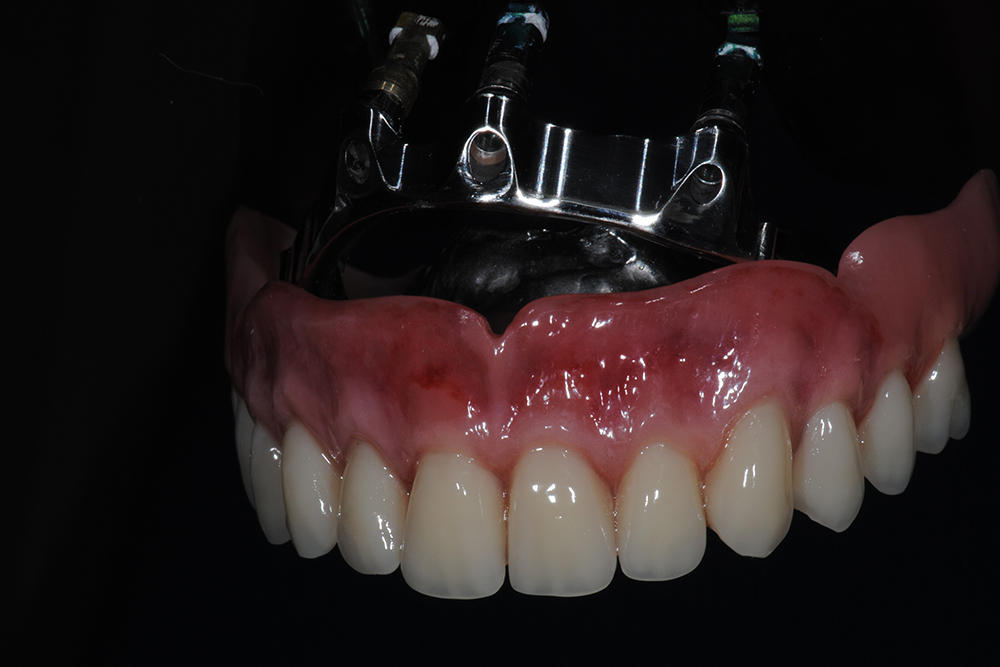

Ripristino dell’arcata superiore ed inferiore su overdenture su barra